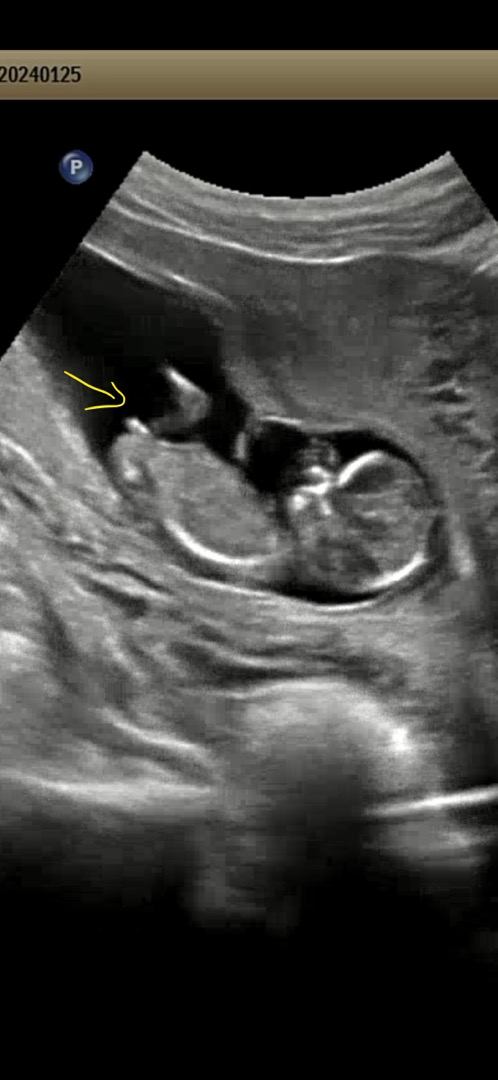

제가 아는 선에서 말씀드릴게요 신뢰할 수 없는 전문적 지식은 아닙니다😁 12주 정밀초음파 검사하실 때 다들 영상을 받으셨을거에요 초음파 영상을 다운받으시고 천천히 다시 재생해서 보시면서 1. 옆모습 자세 중에서 2. 생식기 위치를 중심적으로 본다 3. 뭔가 하얀색으로 생식기 모양이 보인다면 4. 캡쳐하기 생식기 뻗어있는 각도가 허벅지뼈나 척추뼈와 평행하다면 딸 살짝 위로 솟아?있으면 아들 같은 옆모습 자세라도 생식기가 찍히는 경우와 안 찍히는 경우가 있어서 영상 보시면서 생식기 찍힌걸 찾는게 중요해요!! 조금이라도 도움되셨음 좋겠어요^^ 저희 둘째 같은 경우는 매우 선명하게 생식기가 보이지만 아무래도 딸 같죠? 아닐까요! ㅎㅎㅎ

저두 아들같아용 딸은 화살표 표시해두신곳 끝이 갈라져있고 아들은 사진처럼 갈라져있지않더라구용

평행해서 딸같아요~^^